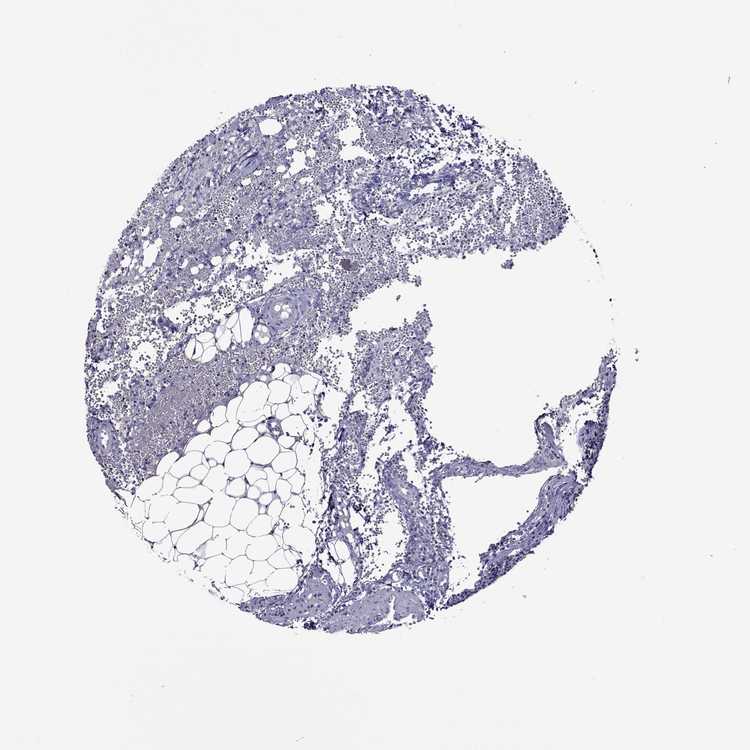

TISSUE PRIMARY DATA LYMPH NODE Show tissue menu

Lymph node

LYMPH NODE - Antibody stainingi

Antibody staining in the annotated cell types in the current human tissue is reported as not detected, low, medium, or high, based on conventional immunohistochemistry profiling in selected tissues. This score is based on the combination of the staining intensity and fraction of stained cells.

Each image is clickable and will lead to virtual microscopy that enables deeper exploration of all samples and also displays staining intensity scores, fraction scores and subcellular localization as well as patient and tissue information for each sample.

Antibody HPA074762Antibody CAB075684

Germinal center cells Not detectedNot detected

Non-germinal center cells Not detectedNot detected